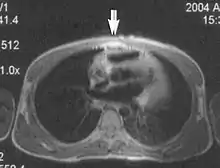

A motion artifact is one of the most common artifacts in MR imaging.[2] Motion can cause either ghost images or diffuse image noise in the phase-encoding direction. The reason for mainly affecting data sampling in the phase-encoding direction is the significant difference in the time of acquisition in the frequency- and phase-encoding directions.[1] Frequency-encoding sampling in all the rows of the matrix (128, 256 or 512) takes place during a single echo (milliseconds). Phase-encoded sampling takes several seconds, or even minutes, owing to the collection of all the k-space lines to enable Fourier analysis. Major physiological movements are of millisecond to seconds duration and thus too slow to affect frequency-encoded sampling, but they have a pronounced effect in the phase-encoding direction. Periodic movements such as cardiac movement and blood vessel or CSF pulsation cause ghost images, while non-periodic movement causes diffuse image noise (Fig. 1). Ghost image intensity increases with amplitude of movement and the signal intensity from the moving tissue. Several methods can be used to reduce motion artifacts, including patient immobilisation, cardiac and respiratory gating, signal suppression of the tissue causing the artifact, choosing the shorter dimension of the matrix as the phase-encoding direction, view-ordering or phase-reordering methods and swapping phase and frequency-encoding directions to move the artifact out of the field of interest.[1]

Flow can manifest as either an altered intravascular signal (flow enhancement or flow-related signal loss), or as flow-related artifacts (ghost images or spatial misregistration). Flow enhancement, also known as inflow effect, is caused by fully magnetised protons entering the imaged slice while the stationary protons have not fully regained their magnetization.[1] The fully magnetized protons yield a high signal in comparison with the rest of the surroundings. High velocity flow causes the protons entering the image to be removed from it by the time the 180-degree pulse is administered. The effect is that these protons do not contribute to the echo and are registered as a signal void or flow-related signal loss (Fig. 2).[1] Spatial misregistration manifests as displacement of an intravascular signal owing to position encoding of a voxel in the phase direction preceding frequency encoding by time TE/2.The intensity of the artifact is dependent on the signal intensity from the vessel, and is less apparent with increased TE.[1]